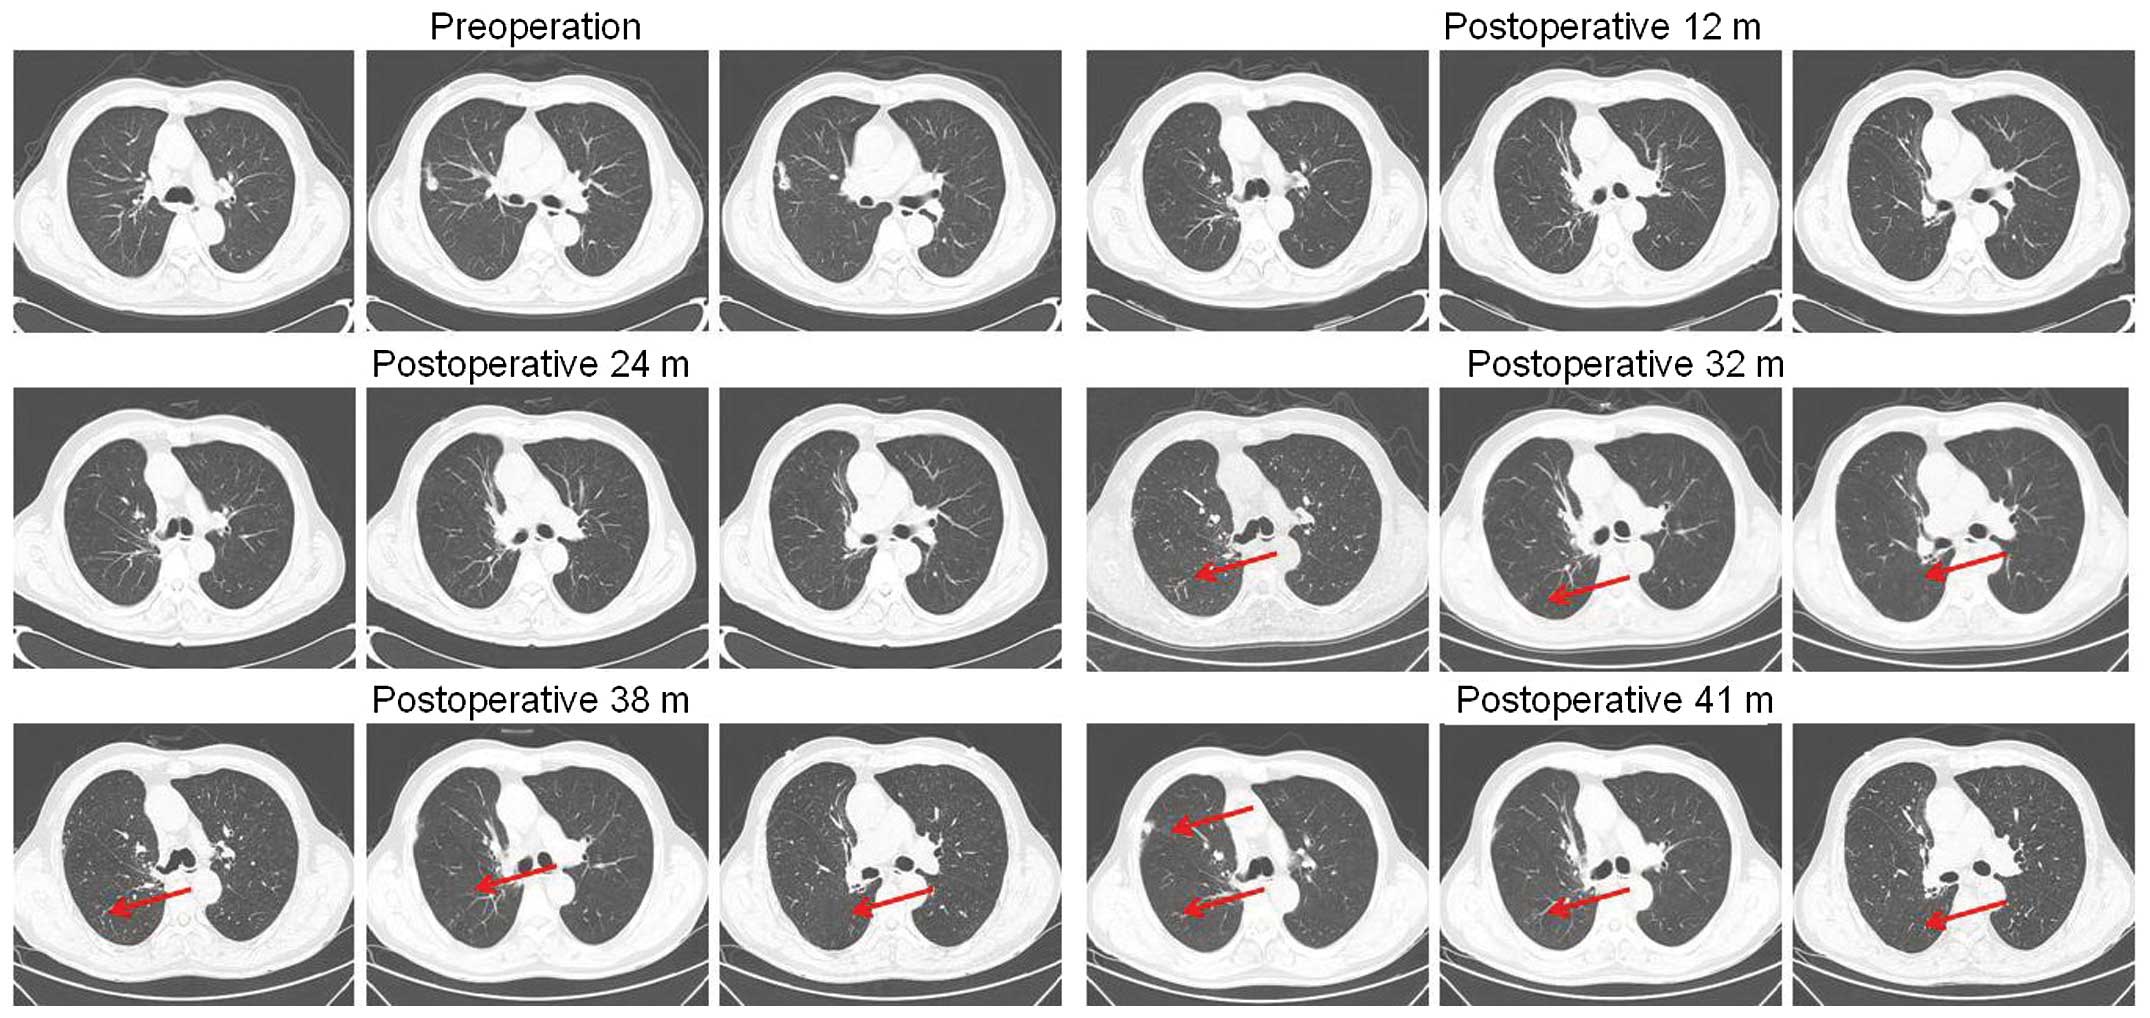

Misjudgement Of Gefitinib Efficacy In Patients With Central Non Small Cell Lung Cancer Due To Obstructive Atelectasis Caused By Stereotactic Radiotherapy

www.spandidos-publications.com